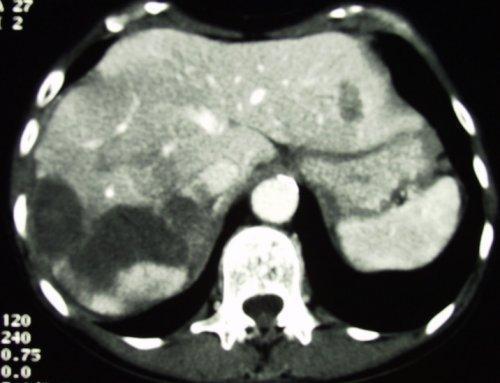

同一病人的随访情况

![]()